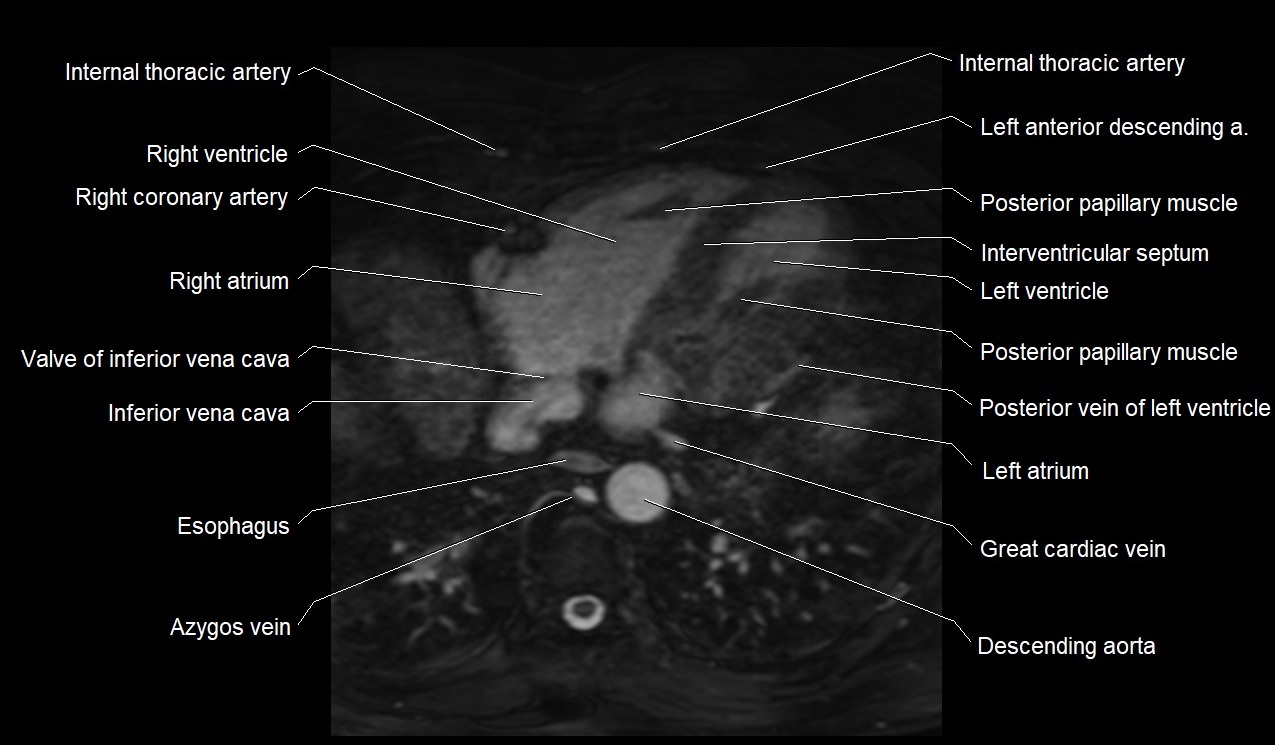

MRI image